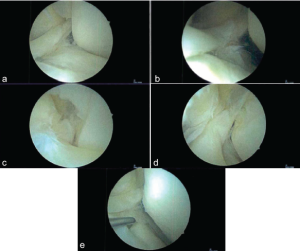

Figure 2: (a-g) Patient 1’s anterolateral meniscofemoral ligament viewed through an anteromedial arthroscopic porthole.

During arthroscopy, there were grade 1–2 changes in the patellofemoral compartment and grade 2 changes in the medial compartment. A radial tear noted in the midsubstance of the medial meniscus was debrided to stable edges. There were grade 2 and minor grade 3 changes in the lateral compartment. The lateral compartment showed abnormal meniscal anatomy evidenced by a partial discoid meniscus with a large intra-meniscal attachment connecting the anterior and posterior horns through the notch. This portion was unstable and mobile, while the midportion of the meniscus in its normal location had complex tearing. The midsubstance of the meniscus was debrided to stable edges, performing a partial meniscectomy. The unstable intra-meniscal attachment connecting the anterior and posterior horns was also debrided. In addition, a separate attachment from the anterior horn of the lateral meniscus to the native ACL origin on the medial aspect of the lateral femoral condyle was found (Fig. 5). This anomalous tissue was debrided. The anterior horn was attached to the root and was stable, and the posterior horn had a partial root attachment and a large meniscofemoral ligament attachment, making it stable. There was no evidence of ACL present in the notch, but the bony anatomy of the notch was normal. Therefore, the decision was made to debride the redundant tissue, restoring normal meniscal shape. On post-operative review of the patient’s MRI, the ALMFL could be appreciated on both the coronal and sagittal images inserting into the native ACL footprint (Fig. 4).

Figure 5: (a-e) Patient 2’s anterolateral meniscofemoral ligament viewed through an anteromedial arthroscopic porthole.